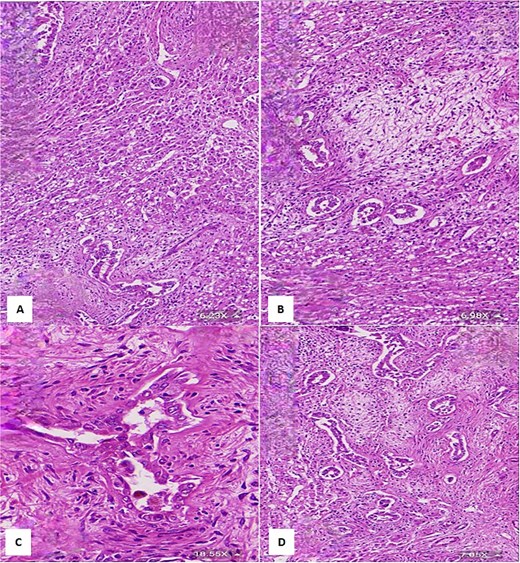

Final histopathological examination of the resected 17 cm mass confirmed the diagnosis of HMH (Figs 4 and 5). The patient recovered well postoperatively.

(A) Histological section showing interspersed islands of hepatocytes with retention of normal cell plate architecture (hematoxylin & eosin, 6.23×). (B) Myxoid area with benign duct structures and interspersed normal hepatocytes (hematoxylin & eosin, 6.98×). (C & D) Dilated and branching bile ducts show no cytological atypia (hematoxylin & eosin: C- 18.55×, D- 7.05×).